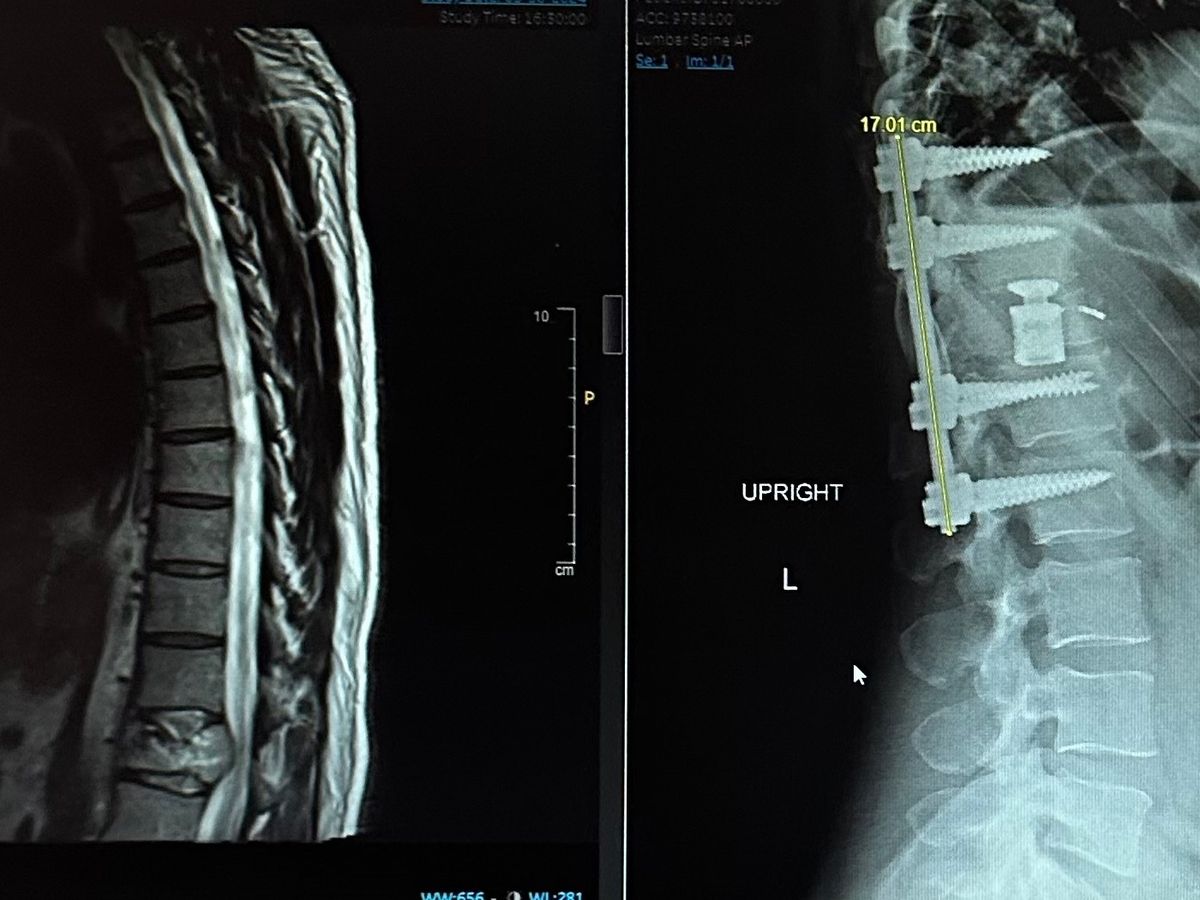

Jay has been battling back pain for quite some time now and went in to the Whitefish ER on Friday, March 29. They did a CT scan to find a tumor degrading the vertebrae and pinching his spinal cord which destabilized the structure of his spine. They life flighted him out to Billings for an emergency surgery. This 16 hour surgery was intense but successful in removing the tumor from the spinal cord area and stabilizing the vertebrae.

During this, the scans have shown Jay has cancer in his spine, pelvis, kidneys, lungs and ribs.